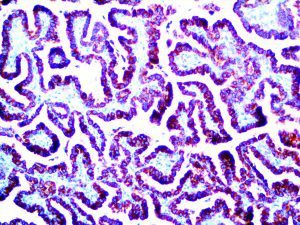

This activation induces inflammatory monocytes to highly express IL-6, starting a localized and then systemic cascade effect that results in hyperproduction of IL-6, which accelerates the inflammatory process. Because IL-6 also increases vascular permeability, excessive levels cause blood vessels to become very leaky. This, along with clotting factors released from vascular endothelial cells, stimulates the coagulation cascade, resulting in microthrombosis (tiny clots), which leads to ischemia and tissue death of the kidney, intestines, heart, liver, brain and extremities.